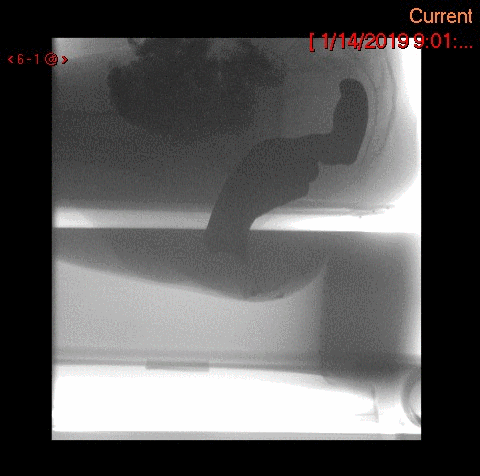

- Ensure that the most proximal side hole is inside the gastric body and obtain a spot film demonstrating the tube in the correct position

(key image 1).

- The most proximal side hole is indicated by a break in the radiopaque stripe on the tube.

- In the image above, it is indicated by the yellow arrow.